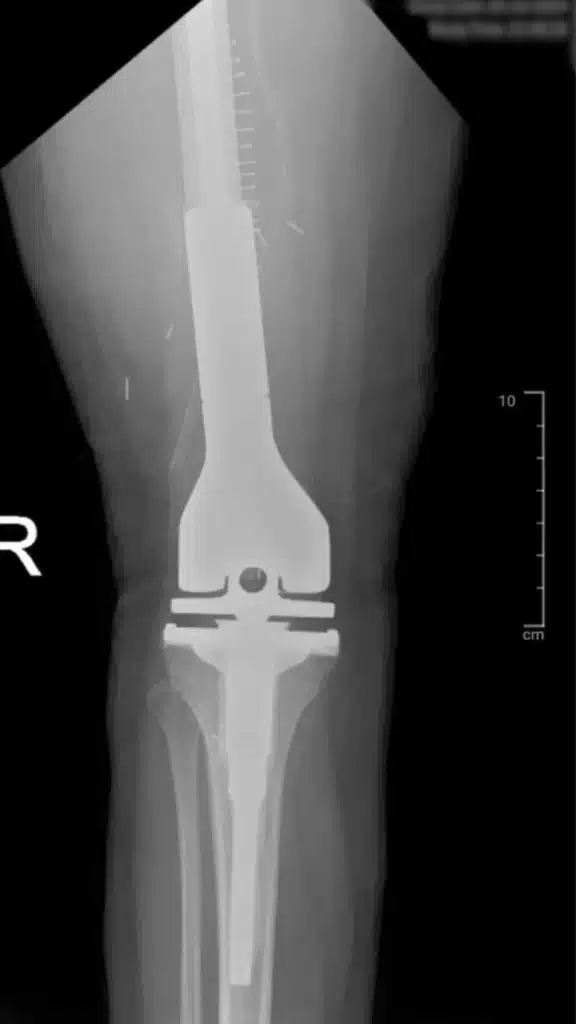

After the tumor has been successfully removed, the bone is reconstructed. This post-operative X-ray image shows the implantation of a modular prosthetic system. The implant replaces the removed distal femur and reconstructs the knee joint, restoring skeletal integrity.